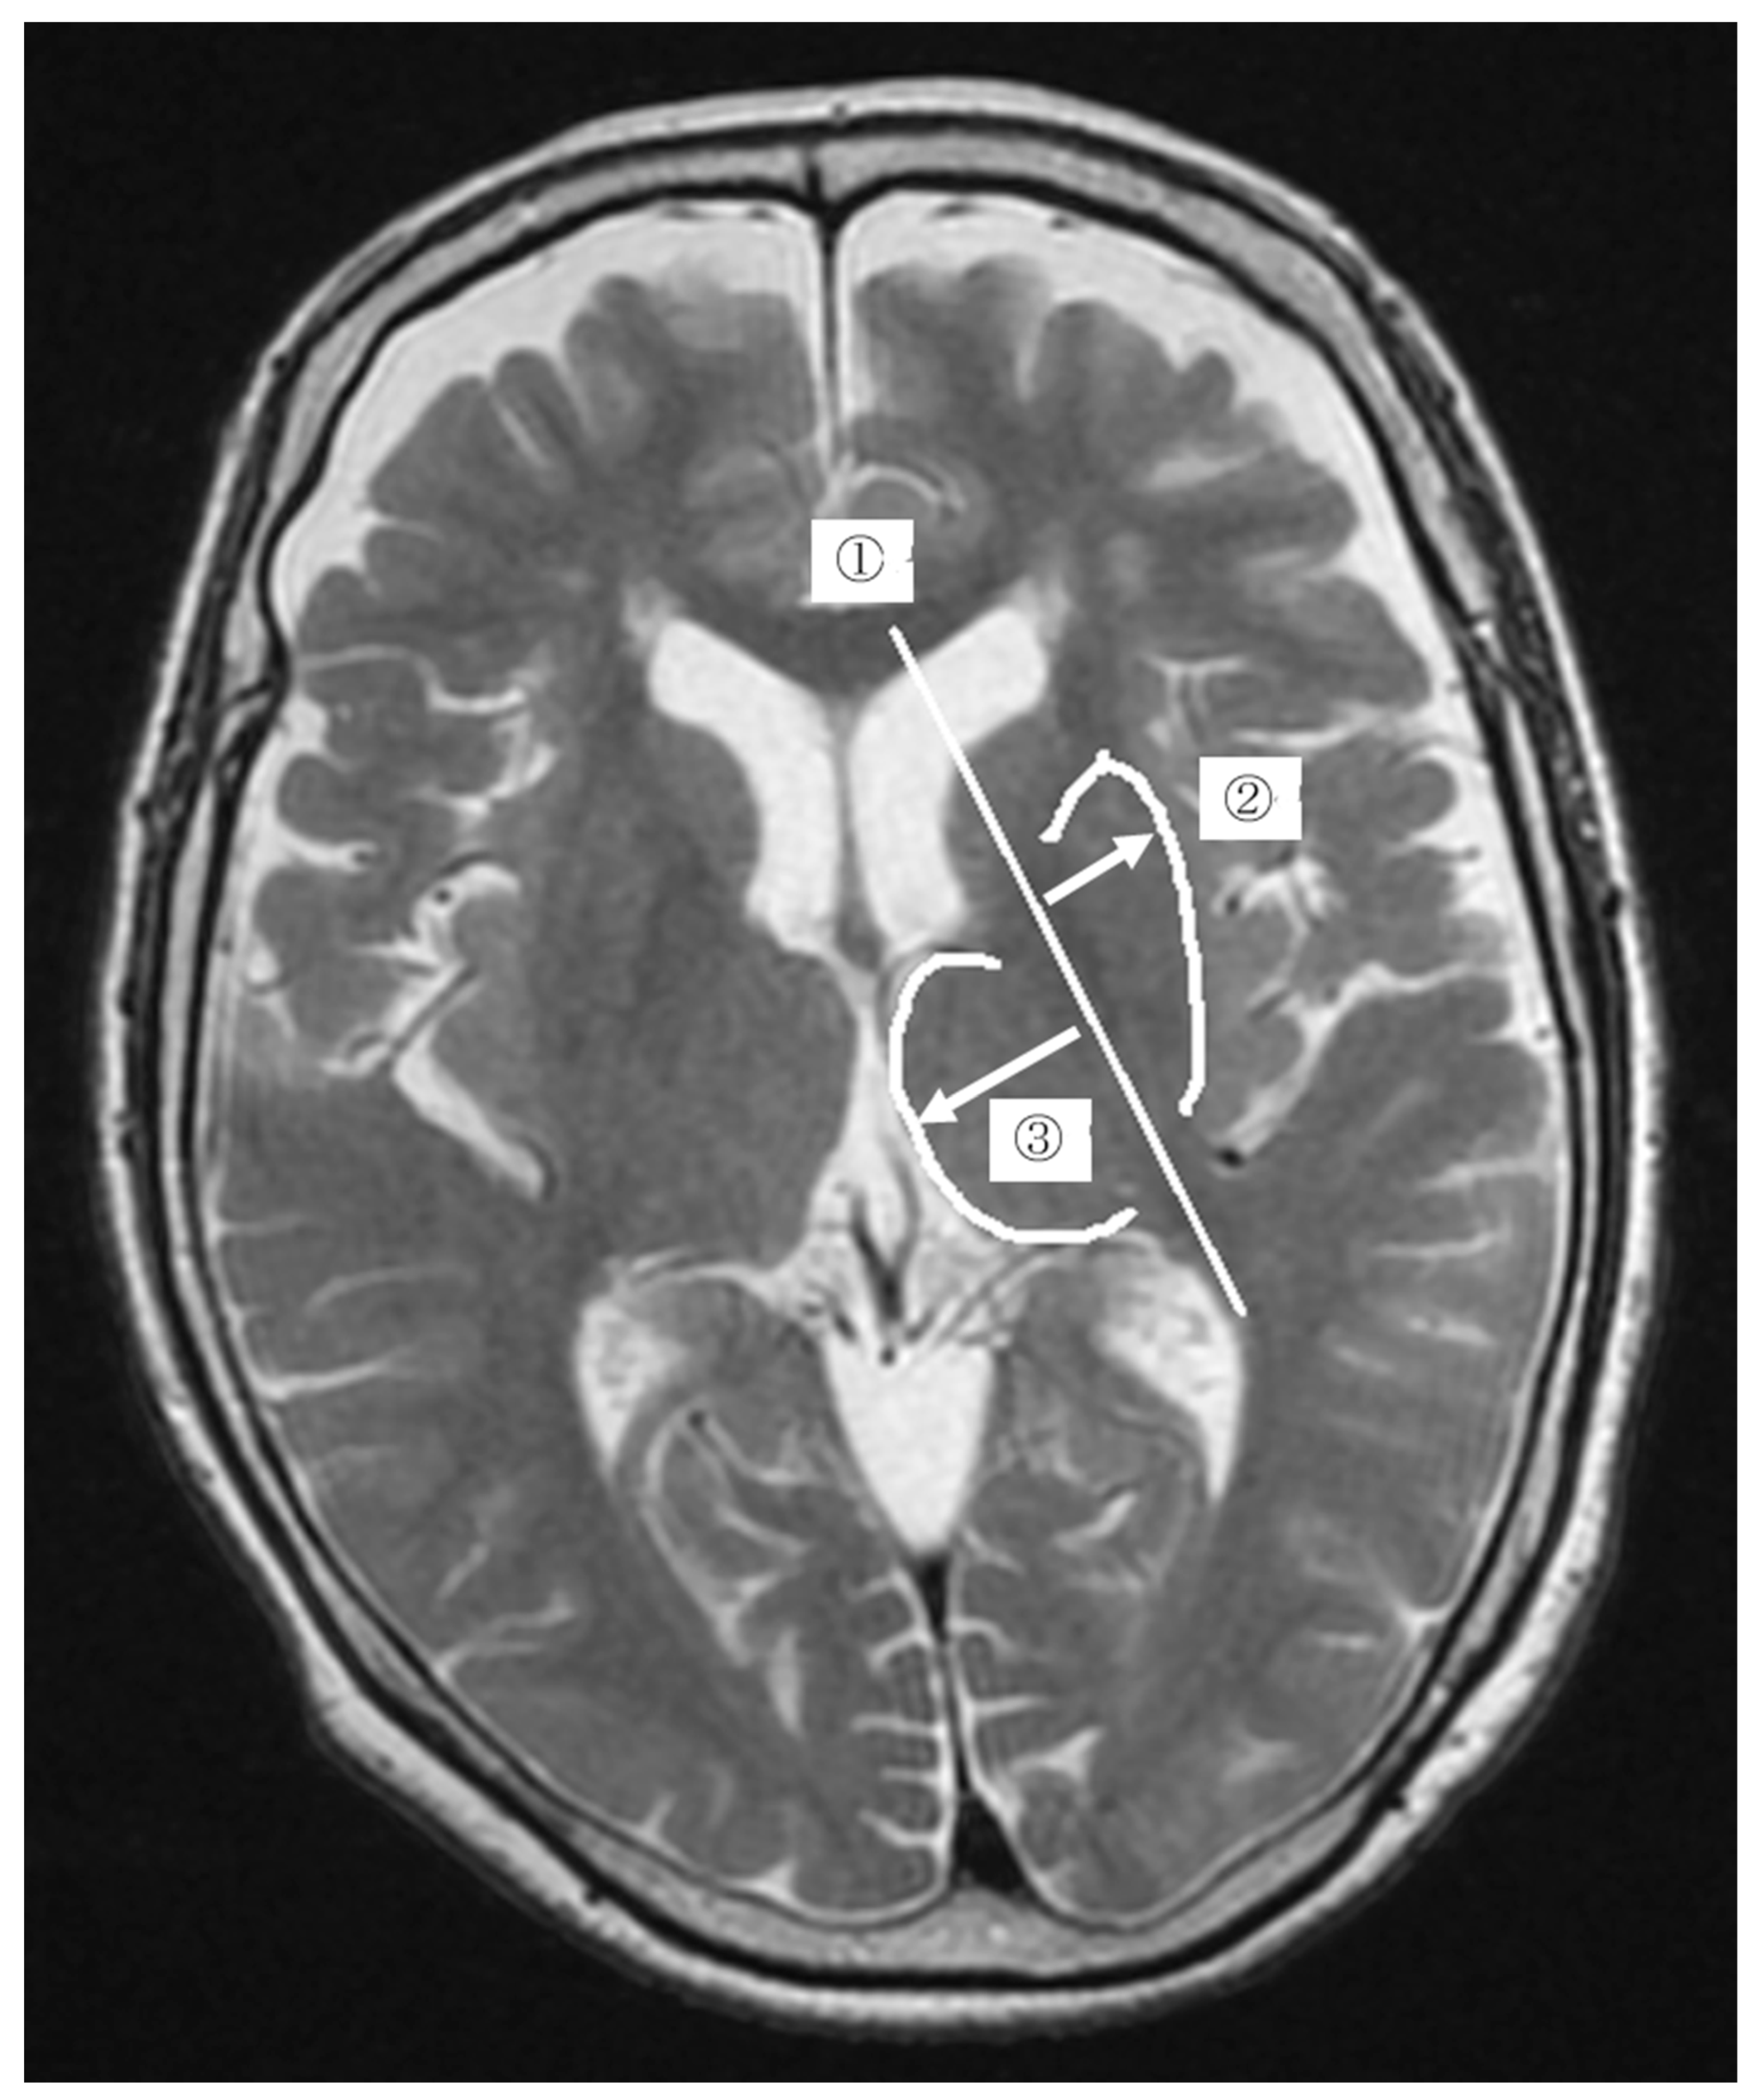

2.3. Measurement Method